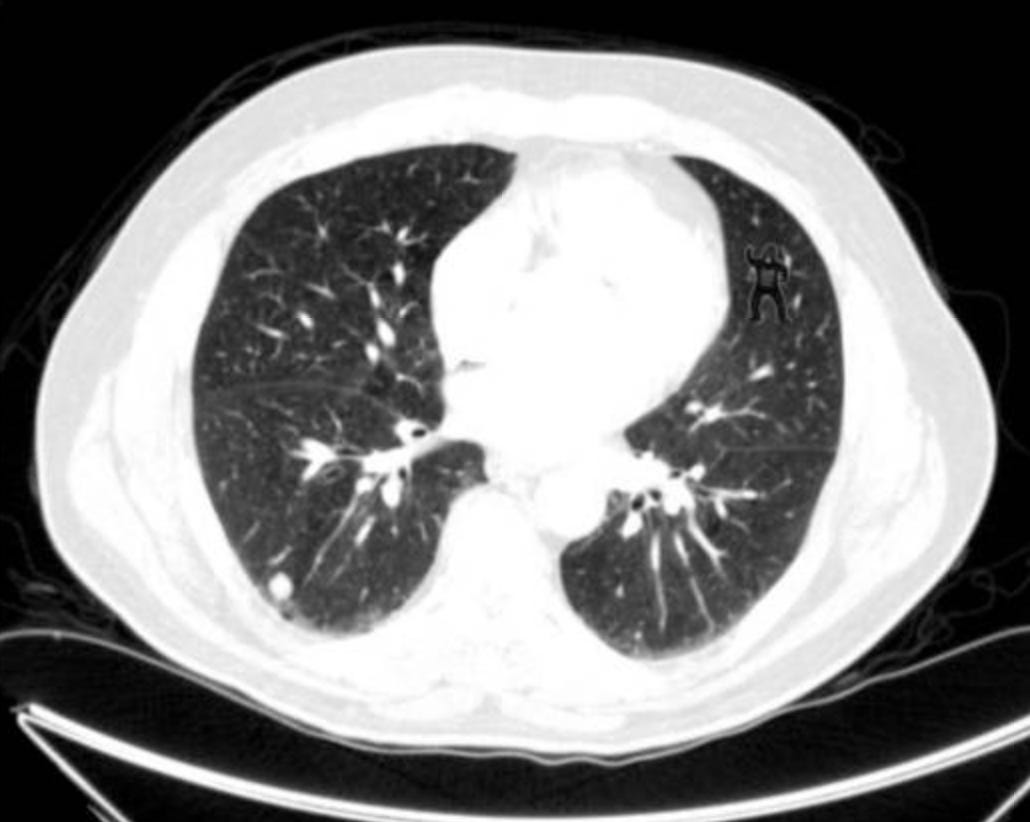

An experiment in 2014 asked 24 radiologists to perform a familiar lung nodule detection task. A gorilla, 48 times larger than the average nodule, was inserted in the last case. 83% of radiologists did not see the gorilla. Eye-tracking revealed that the majority of those who missed the gorilla looked directly at the location of the gorilla. Even expert searchers, operating in their domain of expertise, are vulnerable to inattentional blindness. Full study here: https://pmc.ncbi.nlm.nih.gov/articles/PMC3964612/#:~:text=83%25